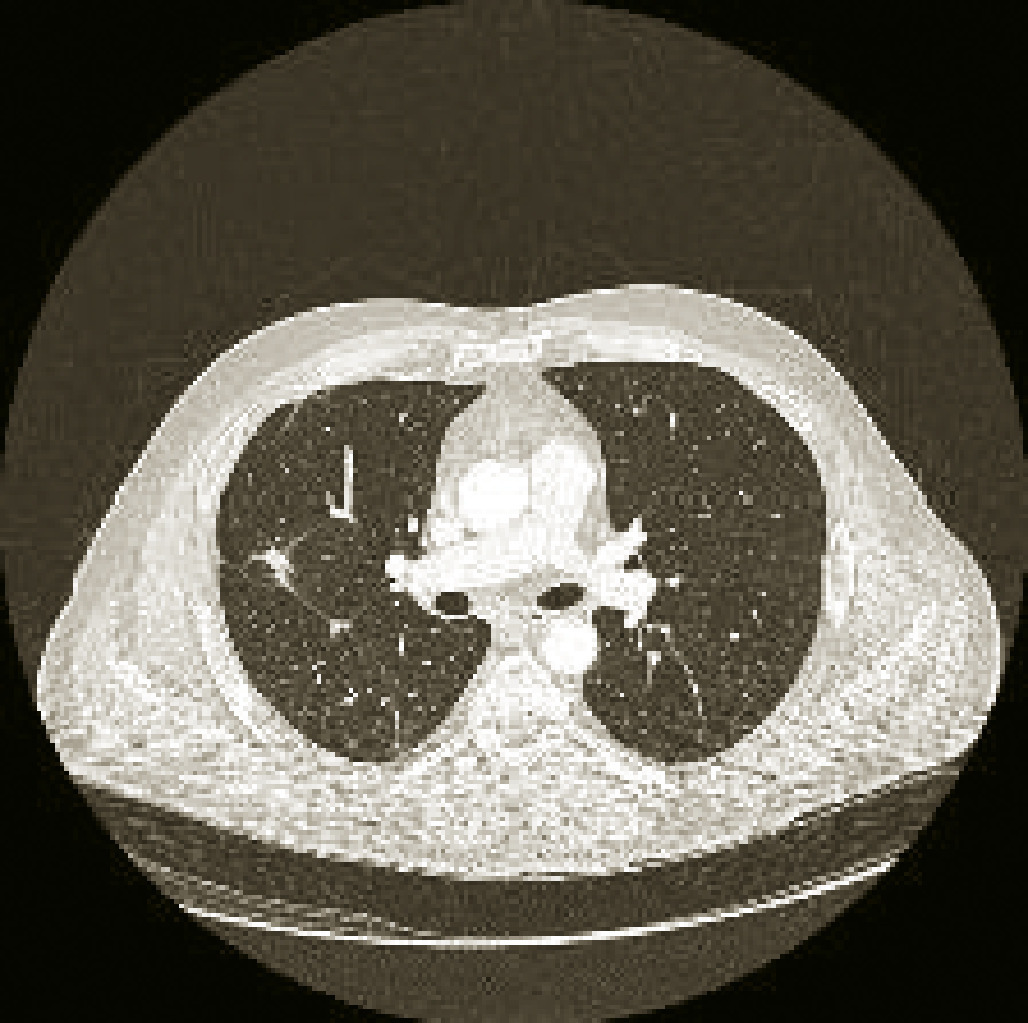

Voici ci-contre, afin d’illustrer l’importance à accorder à la recherche et la découverte de mutations d’intérêt thérapeutique, le cas d’un homme de 51 ans, non-fumeur, chez qui l’on découvre un adénocarcinome bronchique stade IV avec envahissement pleural et ganglionnaire majeur. Lafigure 1 correspond à son imagerie thoracique avant traitement, la figure 2 à son imagerie de réévaluation après traitement par un TKI de première génération ciblant sa mutation activatrice de l’EGFR.•

Voici ci-contre, afin d’illustrer l’importance à accorder à la recherche et la découverte de mutations d’intérêt thérapeutique, le cas d’un homme de 51 ans, non-fumeur, chez qui l’on découvre un adénocarcinome bronchique stade IV avec envahissement pleural et ganglionnaire majeur. La